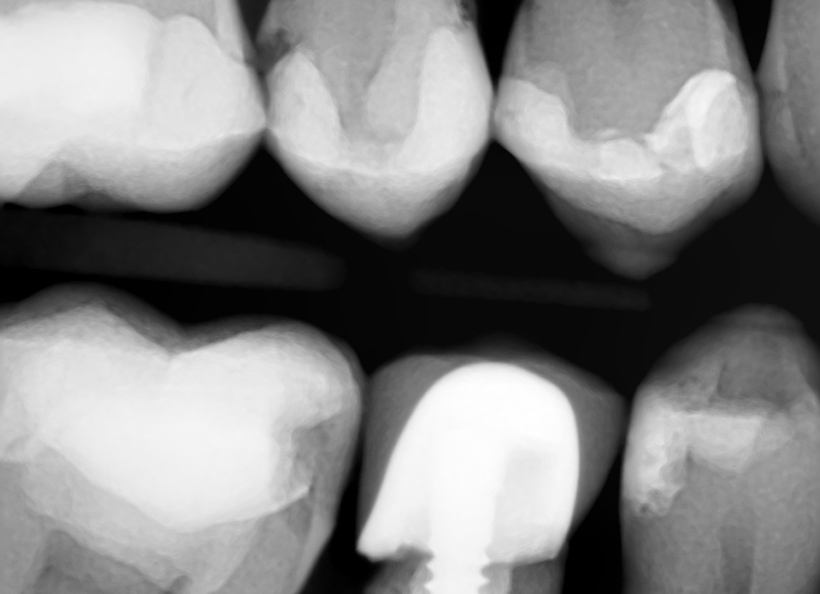

Radiografia digitală bitewing (muşcată) este o radiografie ce oferă informaţii precise (la fel ca şi radiografia retroalveolară) pe o zonă limitată a cavităţii bucale. Pe această radiografie medicul stomatolog poate vedea coroanele dinţilor, atât a dinţilor de pe maxilar, cât şi de pe mandibulă, cât şi rădăcina acestora. Este indicată în cazul cariilor interdentare, retracţiilor ososase, pungilor parodontale, etc.